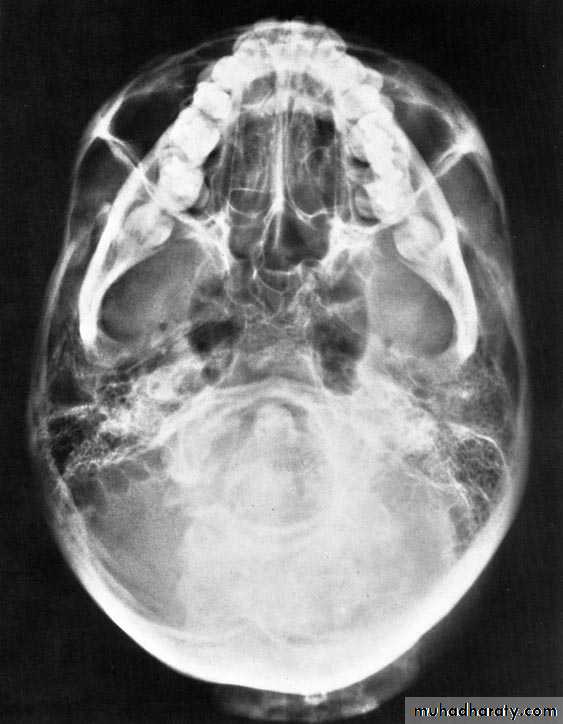

3-Zygomatic fractures:

• A-Plain film: which have limited role in the radiological evaluation of facial trauma. Include:

• -Submentvertex view for zygomatic arch.

Submentovertex view